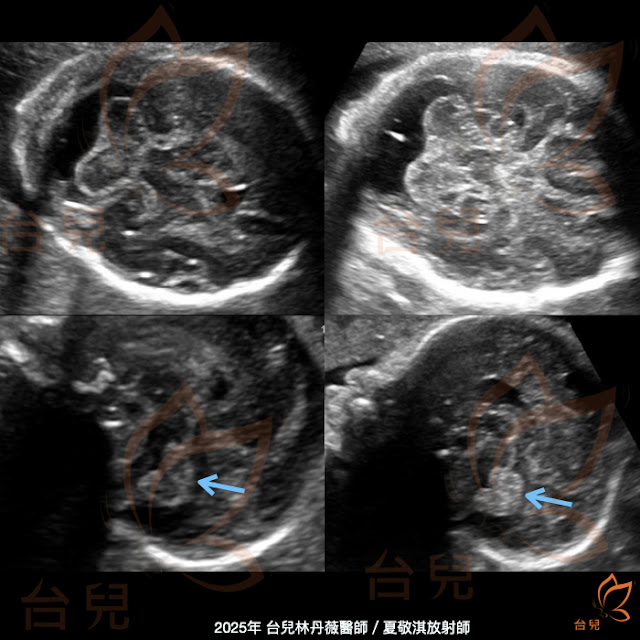

| (圖一) |

此位個案由高雄榮總陳其葳醫師轉介,主訴有胼胝體部份發育不全(partial agenesis of the corpus callosum)和枕大池擴大(enlarged cisterna magna)。

妊娠24週4天在台兒診所進行中期胎兒結構篩檢,超音波影像發現透明中膈腔(CSP)較不對稱(圖一)、部份胼胝體發育不全(圖二、圖三)、枕大池擴大但小腦蚓部正常型態(圖四),此個案的胼胝體發育不良的部位與過往的經驗不同,部份發育不良的部位常常好發於胼胝體主體(body)的後段和壓部(splenium),然而此個案的缺失部位為膝部(genu)和主體的部份前段,正常型態理應看見胼胝體圍繞在在CSP的前方和上方,於圖2中可看見CSP上方沒有胼胝體,使用彩色都卜勒(color Doppler)卻可以描繪出完整的胼胝周圍動脈(pericallosal artery)(圖三)。